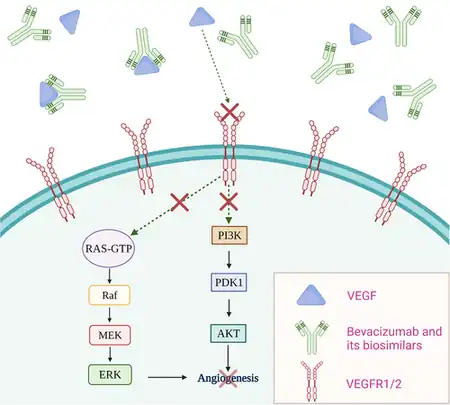

Common side effects when used for cancer include nose bleeds, headache, high blood pressure, and rash.[5] Other severe side effects include gastrointestinal perforation, bleeding, allergic reactions, blood clots, and an increased risk of infection.[5] When used for eye disease side effects can include vision loss and retinal detachment.[5] Bevacizumab is a monoclonal antibody that functions as an angiogenesis inhibitor.[5] It works by slowing the growth of new blood vessels by inhibiting vascular endothelial growth factor A (VEGF-A), in other words anti–VEGF therapy.[5]

Mechanism of action

Bevacizumab is a recombinant humanized monoclonal antibody that blocks angiogenesis by inhibiting vascular endothelial growth factor A (VEGF-A).[46]

VEGF-A is a growth factor protein that stimulates angiogenesis in a variety of diseases, especially in cancer. Bevacizumab was the first available angiogenesis inhibitor in the United States.[47]